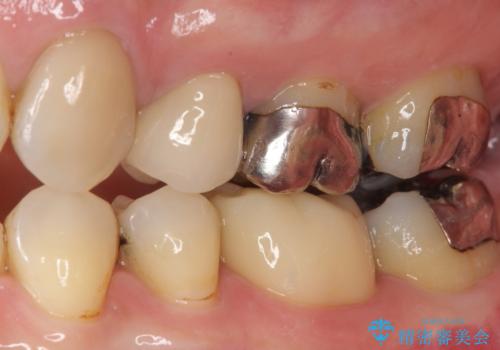

拡大鏡視野下にて、メタルインレーの範囲が大きく虫歯もあったため、オールセラミッククラウンにて修復を行いました。

見た目、噛み合わせともに満足していただけました。